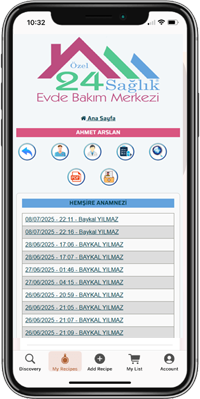

- Süreci cep telefonunuzdan takip edin.

- Hastanıza verilen hizmetleri anında görün.

- Anneniz, babanız, çocuğunuz… Tüm bilgiler tek tıkla elinizde.

- Evde bakımda şeffaflık: Her şey kayıt altında.